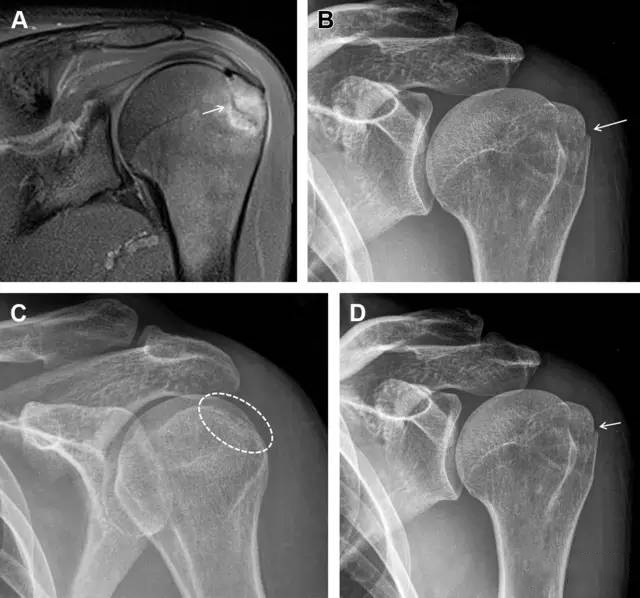

在常规前后位片上,大结节与肱骨头重叠,骨折不易发现,外旋位前后位片有助于诊断。

图1 大结节骨折。(A)脂肪抑制序列斜冠状位 MRI,显示肱骨大结节线性骨折无移位(箭头)与周围骨水肿;(B)外旋位前后位(AP)片,证实大结节骨折(箭头),典型的骨折愈合过程中的骨吸收表现;(C、D)初诊时内旋位、外旋位前后位片,初诊时漏诊,仔细回顾影像,内旋伞下可见双密度影(椭圆),骨皮质中断(箭头)